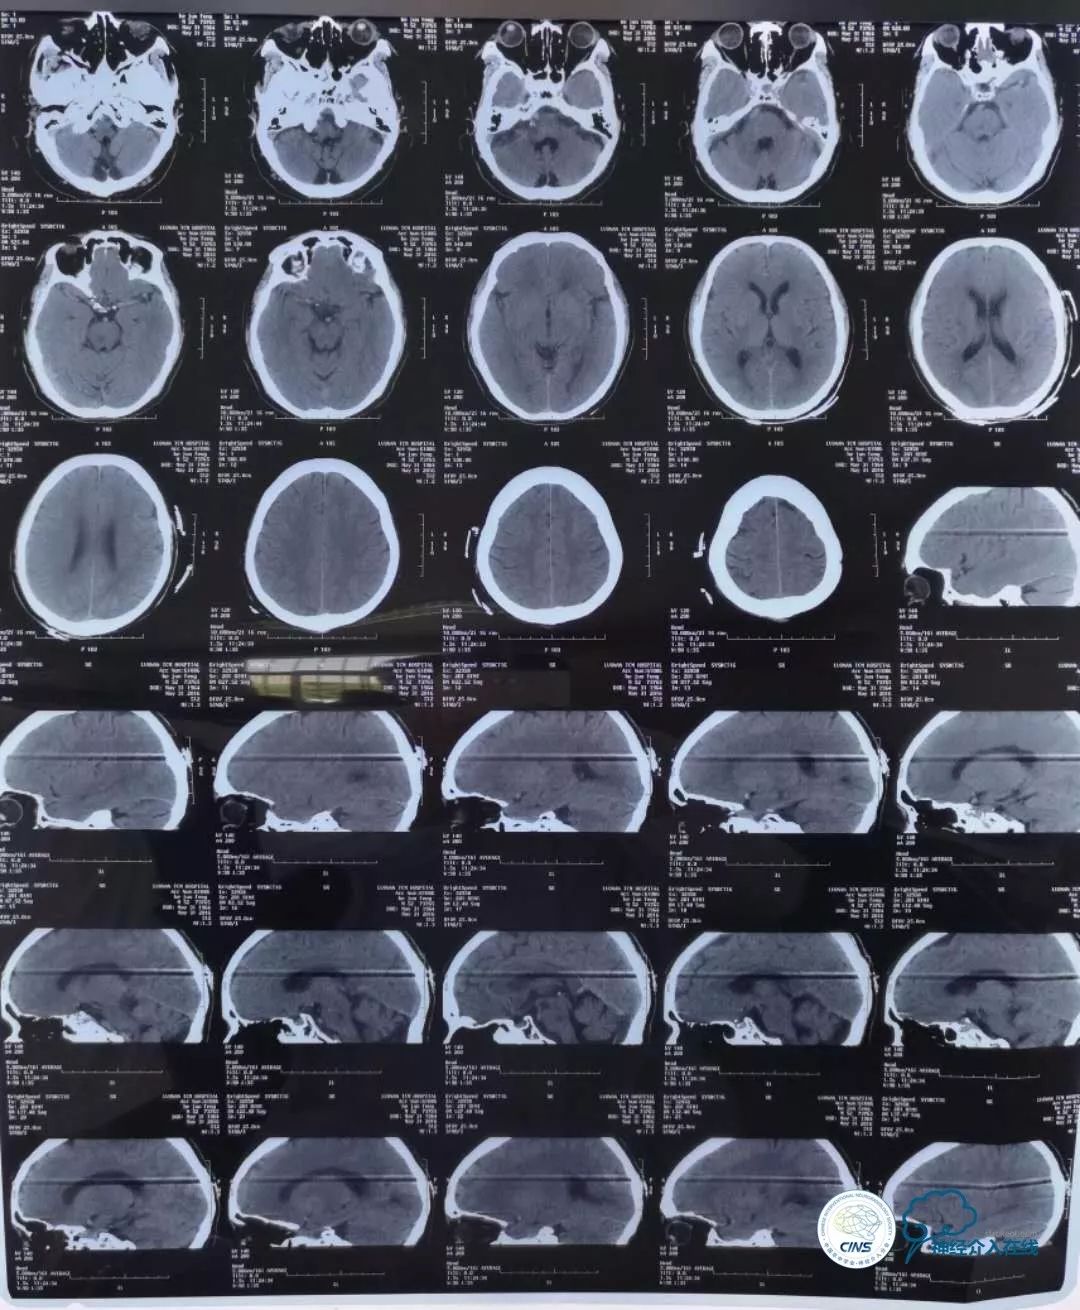

患者男性,53岁,既往脑干梗死,反复晕厥发作,强化药物治疗无效。

彩超示:右椎动脉先天未发育,左椎动脉远端血流受阻。DSA造影如下:

DSA显示,患者右椎动脉发育不良,V2段远端闭塞,仅存的左椎动脉串联病变,V1段迂曲,V4段99%狭窄(并局部溃疡),且病变处发出左小脑后下动脉(PICA),PICA亦99%狭窄,可谓“命悬一线”!